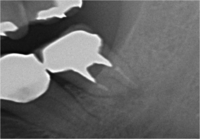

根の先に影(感染)が出てしまい根の治療を行わないといけないのですが以前他院にて処置を施した古い薬が入っています

画像を見ると手前の根にはしっかりと先まで薬が入っていません(1枚目の画像)

根のカーブに対応できず間違った方向へ削り込んでしまっています(赤矢印)

古い薬を除去しとあるテクニックを駆使し正しい根幹への道を見つけました(青矢印)

簡単にやっているように見えますがそのまま器具を入れては大きく間違った道に導かれてしまうなか、その脇から1mmにも満たない狭く曲がった孔を探しそちらへ導くのは至難の技ですが、マイクロスコープとCTを使いしっかりとした手法で行うとこのような症例にも対応できます